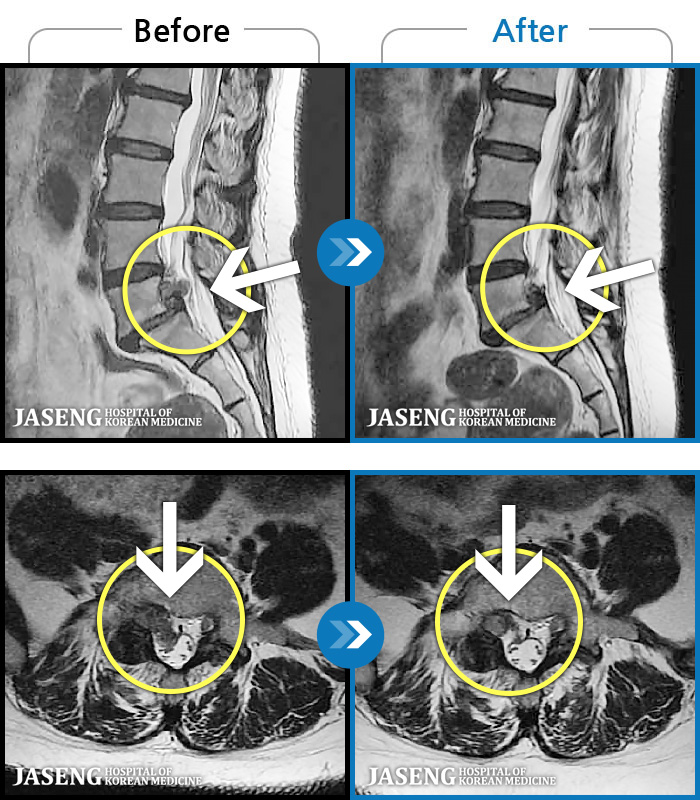

MRI ġ

119 MRI ũ ʸ Ȯϼ.

[Կñ:24.01.30~24.07.09]

[_㸮ũ] ٸ ؼ ɾٴϱ

No.119

ȸ 600

[Կñ:22.08.30~24.08.05]

[_㸮ũ] ٸ ߳ .

No.118

ȸ 506